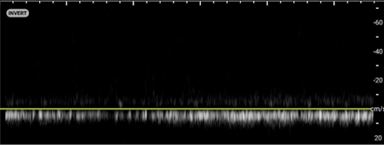

• A healthy testicle should appear oval-shaped and roughly 3–5 cm in length, by 2–3 cm in width depending on the age. Testicles have a homogeneous appearance with a medium-level echogenicity (like other solid organs). They are smooth and uniform throughout when healthy. Start by fanning through the testicle in transverse and longitudinal orientations to get a general assessment. When applying color Doppler to a well perfused testicle, there should be uniform, low velocity arterial and venous blood flow throughout the parenchyma. Vessels may appear pinpoint, linear or branching. Using spectral Doppler, the velocity of specific vessels can be measured. Arterial flow will appear as a brisk upstroke and sharp downstroke reflecting the cardiac cycle. Venous flow has a continuous velocity with less variation, often described as a “venous hum” (Images 6 and 7).7

Torsion - image 6.pngImage 6. Arterial flow on Spectral Doppler.

Torsion - image 7.pngImage 7. Venous flow on Spectral Doppler.